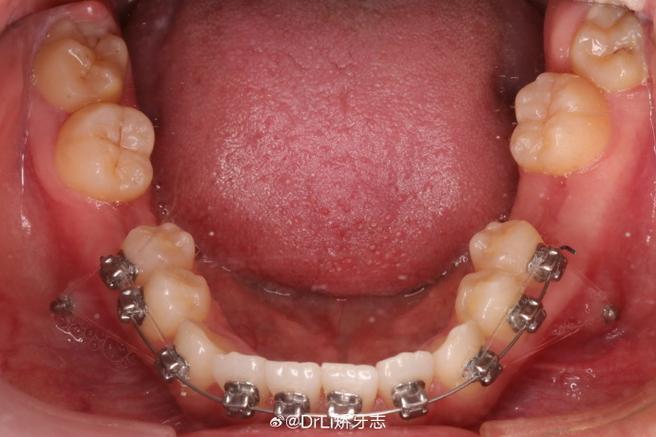

正常咬合状态下,上下颌后牙应稳定支撑于牙槽嵴上,前牙则保持轻度覆盖(上前牙盖过下前牙约1/3),当出现深覆合(上前牙覆盖下前牙过多,甚至下前牙咬到上前牙腭侧)或下颌后缩(下巴位置偏后,上下颌关系不协调)时,单纯通过托槽弓丝可能难以快速调整颌骨关系,斜导通过在口腔内设置特定的斜面结构,改变下颌闭合时的运动路径:当患者咬合时,下颌前牙会沿着斜面向前、向上滑动,从而带动下颌骨及后牙牙槽骨发生适应性改建,逐渐纠正异常咬合。

对于深覆合患者,斜导可压低上前牙、伸长下前牙,增加前牙垂直距离;对于下颌后缩患者,斜导引导下颌向前移动,改善侧面突度(如“月亮脸”或“鸟嘴”畸形),斜导还能暂时性分散咬合力,避免个别牙齿因受力过大而松动或损伤,为后续精细调整奠定基础。

斜面导板是临床最常用的类型,尤其适用于下颌后缩伴深覆合的青少年患者,其斜面角度需精确计算(通常为45°),以确保下颌前移时受力均匀,避免颞下颌关节负担。